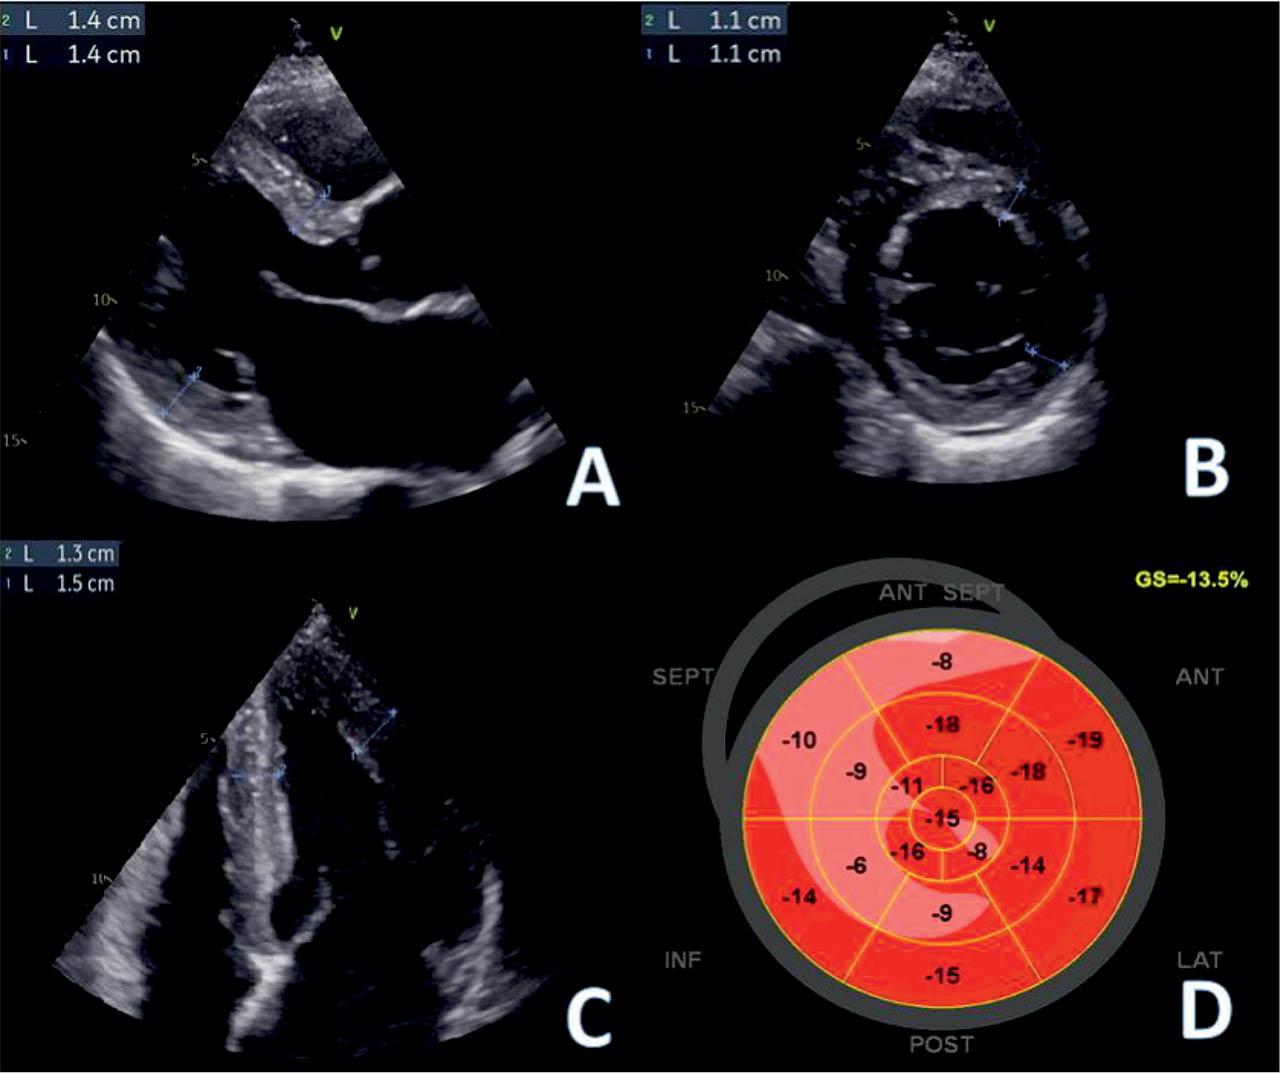

The 2D echocardiography (Figure 3) showed a non-dilated left ventricle (LV), with concentric hypertrophy, especially at the apical level (maximum wall thickness of 15 mm), no left ventricular outflow tract obstruction, a preserved LV ejection fraction (LVEF) and no regional wall motion abnormality; normal right ventricular free wall thickness was measured. Speckle tracking imaging showed a reduced global longitudinal strain (GLS) of −13.5%. Severe left atrial (LA) enlargement and mild functional mitral regurgitation were associated.

Figure 1

Transthoracic echocardiography. Basal anterior septum and posterior wall measurements in panels A. Parasternal long axis view (PLAX) and B. Parasternal short axis at mitral valve level (PSAX- MV). C. Apical four chamber view (A4C) measurements of apical inferior septum and anterolateral wall (maximum thickness 15 mm). D. Myocardial deformation imaging. Longitudinal strain bull’s eye plot showing a reduced global longitudinal strain (−13.5%) with lowest segmental values in septal and inferior segments.

The case is an illustration of bringing together red flags leading to the diagnosis of Fabry disease, an X-linked genetic disease, characterized by a deficiency of the lysosomal enzyme GLA and the pathological accumulation of globotriaosylceramides in the body’s cells, determining various cardiac, neurological, renal and cutaneous manifestations4. Women have long been considered healthy carriers of the GLA mutation, but studies have shown that women can develop phenotypes comparable to those of men, yet with a later onset of cardiovascular manifestations than men5. In addition, in most patients with Fabry disease (76.9%), ischemic stroke occurred before cardiac or renal manifestations6. A short PR interval, commonly found in patients with Fabry disease, is probably caused by accelerated intraatrial conduction7. However, with disease progression, patients may develop atrioventricular or bundle branch blocks, as well as sinus node dysfunction8, features also observed in our case. Although reduction of LV GLS, quantified by two-dimensional speckle tracking is typically found in the basal postero-lateral segments9 of Fabry hearts, in our case the bull’s eye of segmental longitudinal peak strain values assessed by two-dimensional speckle tracking showed lower values in the anteroseptal region.